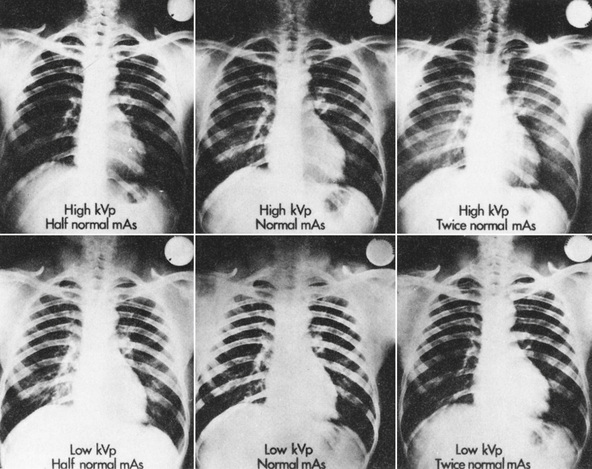

As kVp is increased, both the quantity and quality of x-radiation are increased; a greater number of x-rays are transmitted through the patient, so a higher portion of the primary beam reaches the image receptor. Thus kVp also affects OD. Among x-rays that interact with the patient, the relative number of Compton interactions increases with increasing kVp, resulting in less differential absorption and reduced subject contrast.

Furthermore, with increased kVp, the scatter radiation that reaches the image receptor is greater; therefore, radiographic noise is higher. The result of increased kVp is loss of contrast. When radiographic contrast is low, latitude is high, and the margin for error is increased.

The principal advantages of the use of high kVp include a reduction in patient dose and a wide latitude of exposures allowed in the production of a diagnostic radiograph. Figure 10-36 shows a series of chest radiographs demonstrating increased latitude resulting from a high-kVp technique. The relative technique factors are indicated on each radiograph. To some extent the use of grids can compensate for the loss of contrast accompanying a high-kVp technique.

As the mAs value is increased, the radiation quantity increases; therefore, the number of x-rays arriving at the image receptor increases, resulting in higher OD and lower radiographic noise but higher patient radiation dose.

In a secondary way, the mAs value also influences contrast. Recall that maximum contrast is attained only when the film is exposed over a range that results in OD along the straight-line portion of the characteristic curve. Too low an mAs setting results in low OD and reduced radiographic contrast because the H & D curve has flattened. Too high an mAs value results in high OD and loss of radiographic contrast for the same reason.

The continuing trend in radiographic technique is to use high kVp with a compensating reduction in mAs to produce a radiograph of satisfactory quality while reducing the patient dose and the likelihood of an ordered reexamination because of an error in technique.